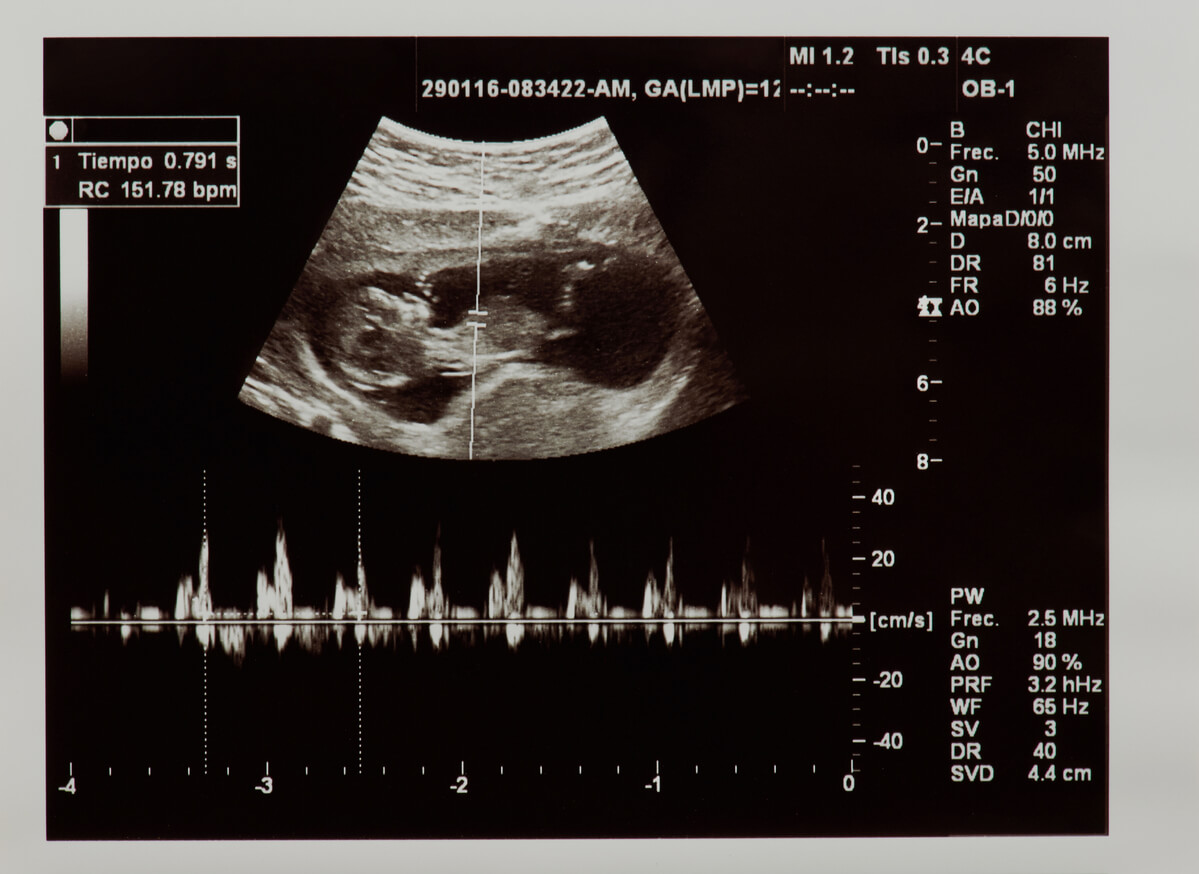

En el conocido hospital de Xalapa, doctores del área de Ginecología habrían informado a la pareja que su bebé murió. Presuntamente, el médico de guardia concluyó a partir de un ultrasonido que se trataba de una amenaza de aborto y aseguró que “ya no había latido fetal”.